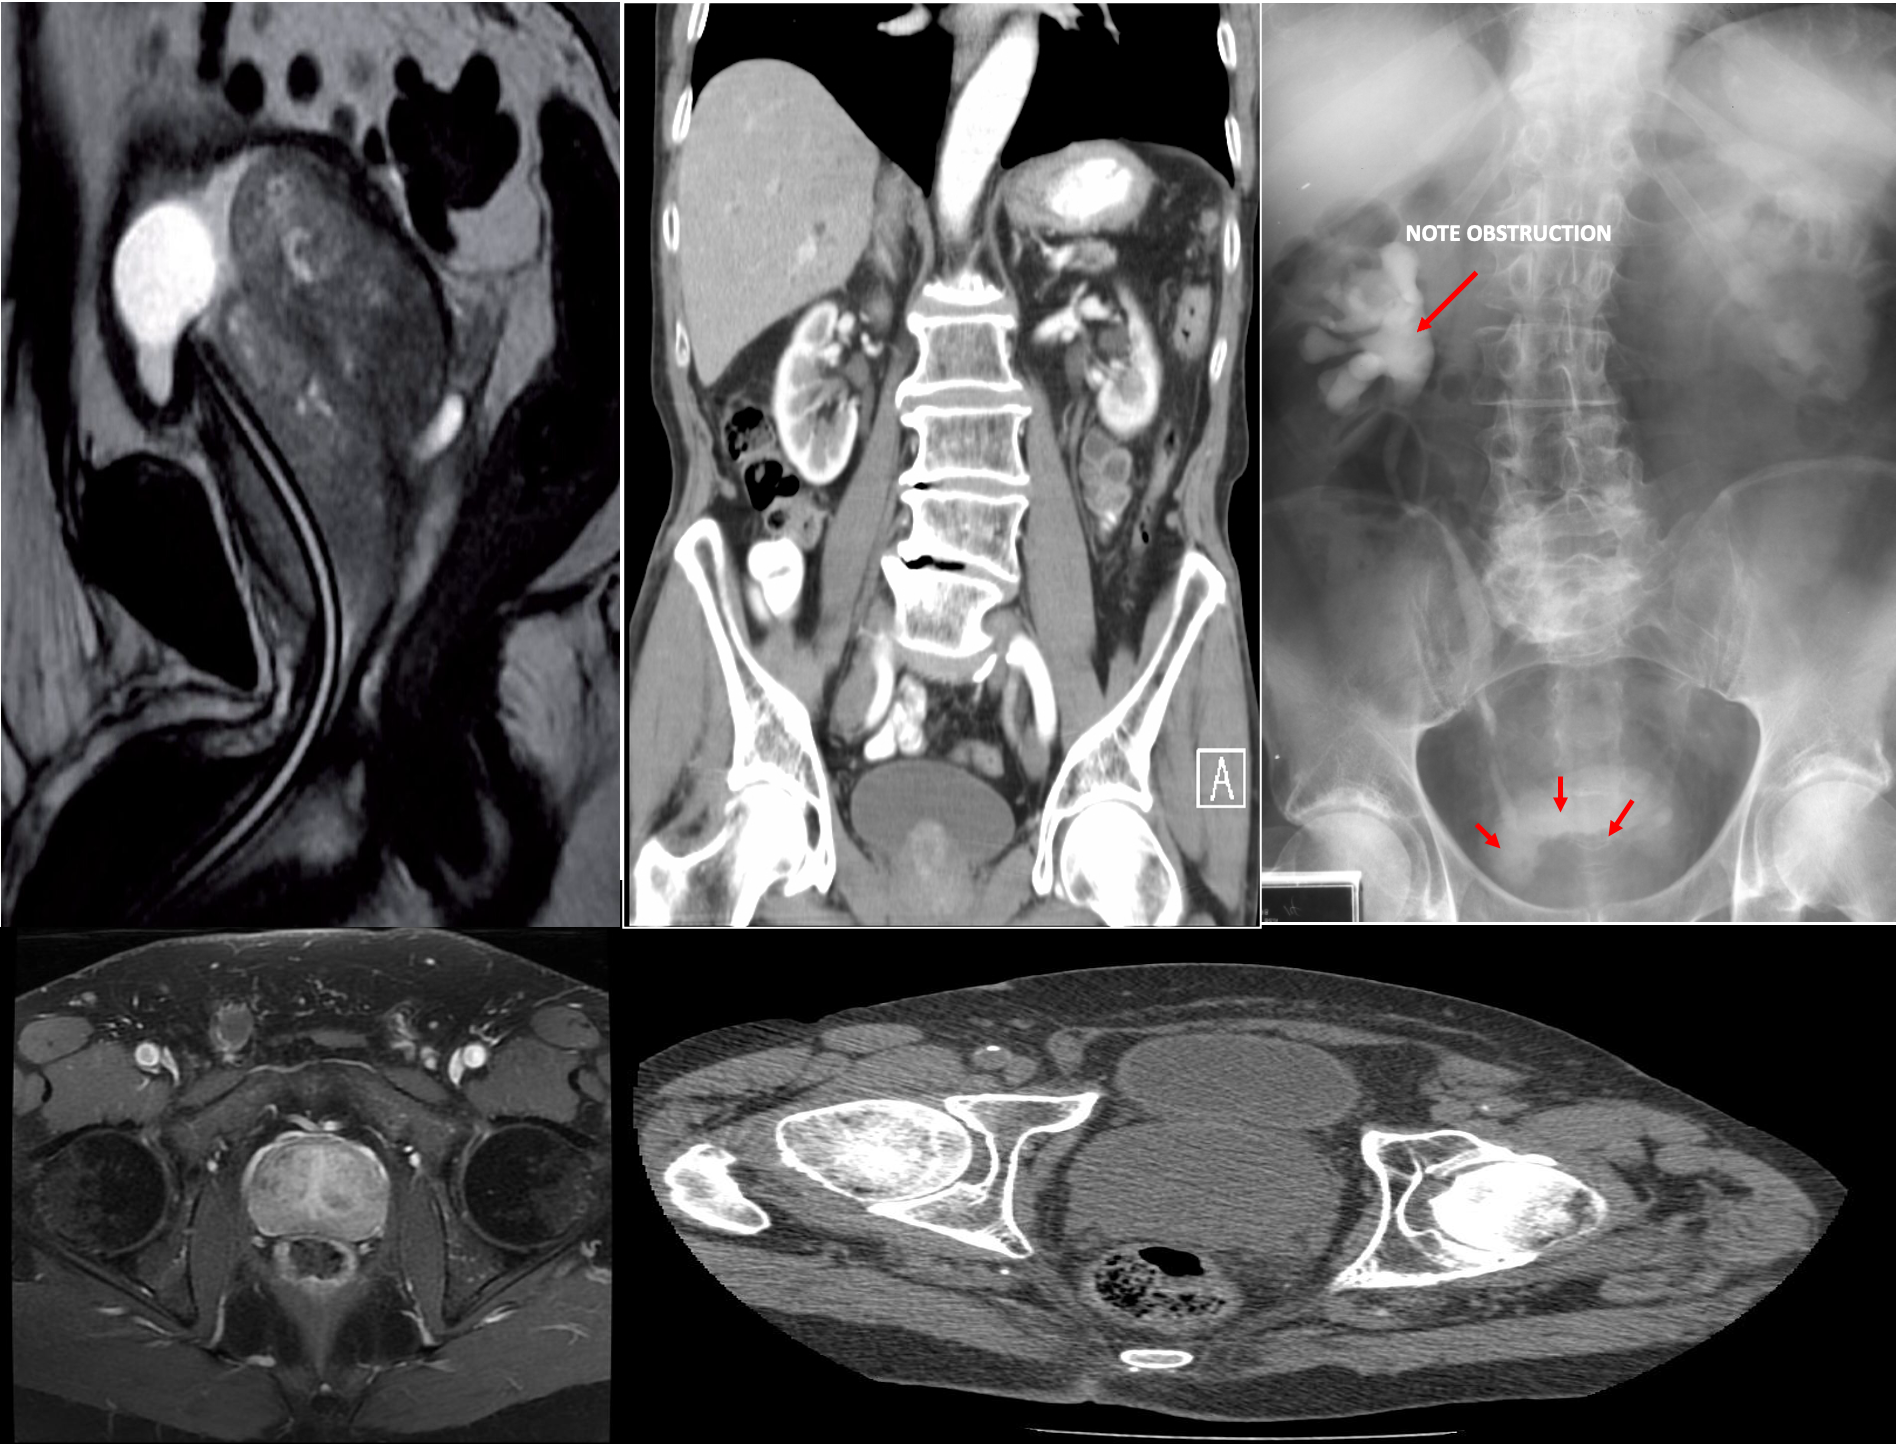

MRI and CT pelvis

Commonly used for preprocedural assessment of prostate volume and localization of enlarged tissue

-

MRI can potentially differentiate BPH from prostate cancer.

Enlarged prostate gland - MRI pelvis (T2-weighted, sagittal plane) The enlarged prostate gland is lobulated and heterogeneous. The bladder base is elevated. A foley catheter is in place.

This can obstruct the ureters entering the bladder leading to hydronephrosis and renal failure.